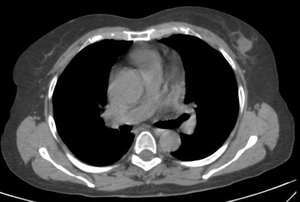

标题: CT2108:乳腺肿物

可见毛刺及淺分叶以乳腺ca可能性大

右侧乳腺退化得差不多了,说明病人年龄较大,左侧却见一这么高密度肿块,周围似乎见到毛刺与牛角征,考虑乳腺癌可能性大。

分叶状肿块,周围见蜘蛛足样征,考虑乳腺癌.